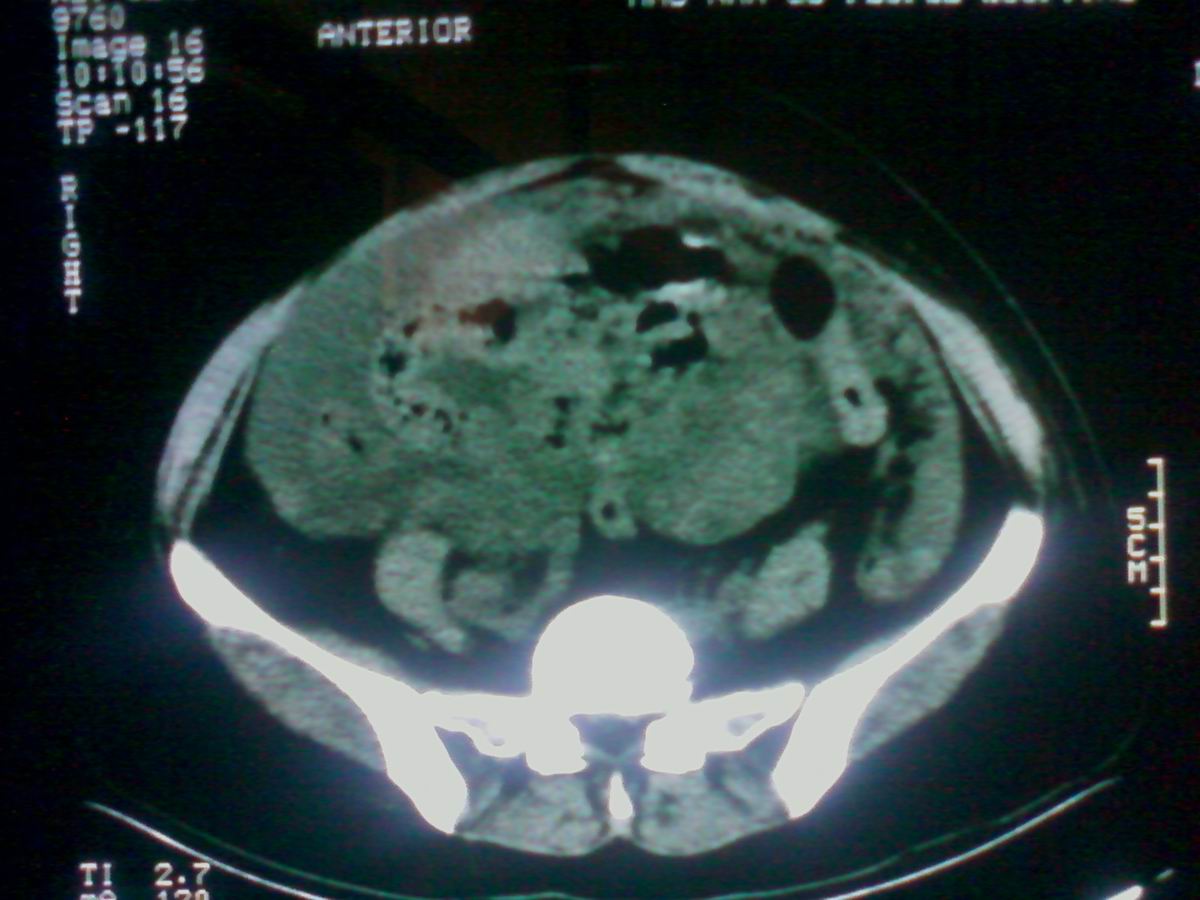

标题: CT25799:女性患者,45岁,腹胀,上腹部疼痛来诊,B超示盆腔 [打印本页]

标题: CT25799:女性患者,45岁,腹胀,上腹部疼痛来诊,B超示盆腔

考虑卵巢癌伴腹水

1)考虑卵巢恶性肿瘤。2)腹水。